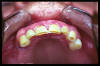

CM Desgaste por bruxismo, presencia de cálculo